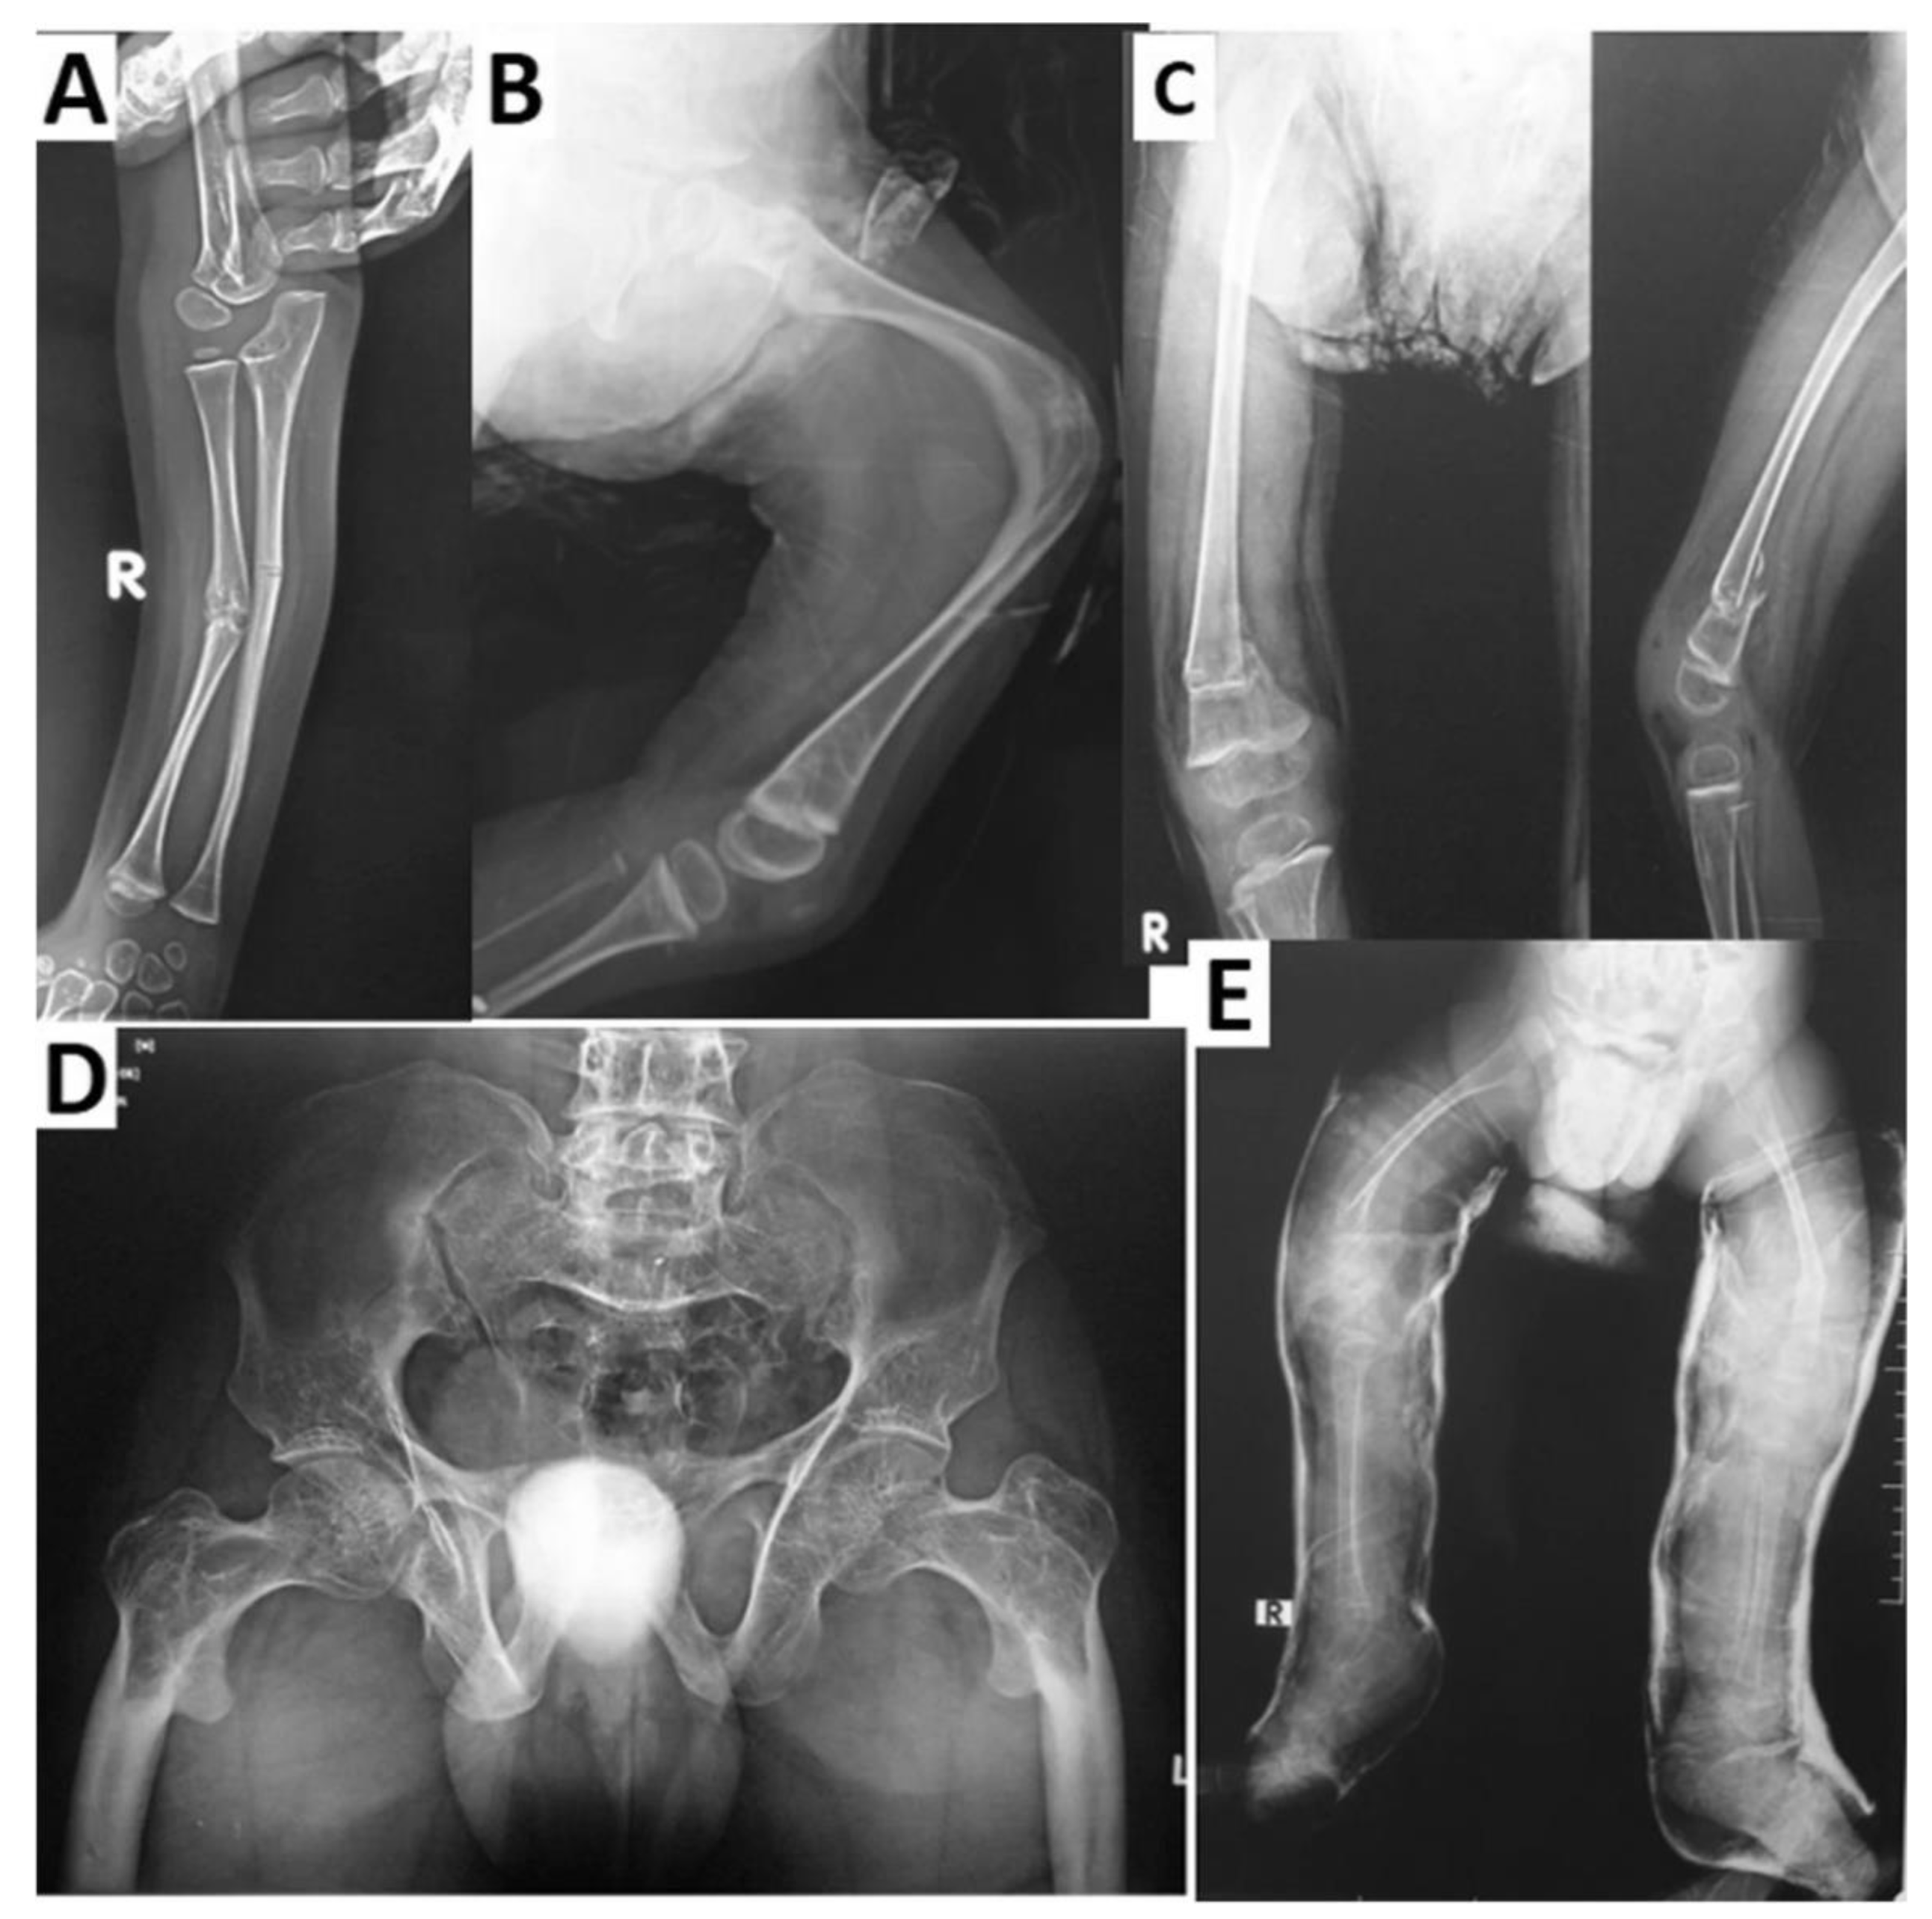

- Littman, J.; Phornphutkul, C.; Saade, C.; Katarincic, J.; Aaron, R. Osteoporosis, Fractures, and Blindness Due to a Missense Mutation in the LRP5 Receptor. Orthop. Res. Rev. 2023, 15, 39–45. [Google Scholar] [CrossRef] [PubMed]